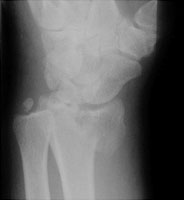

- Click on the image for a larger versionBOblique radiograph of the wrist. The intraarticular nature of this fracture can be appreciated.